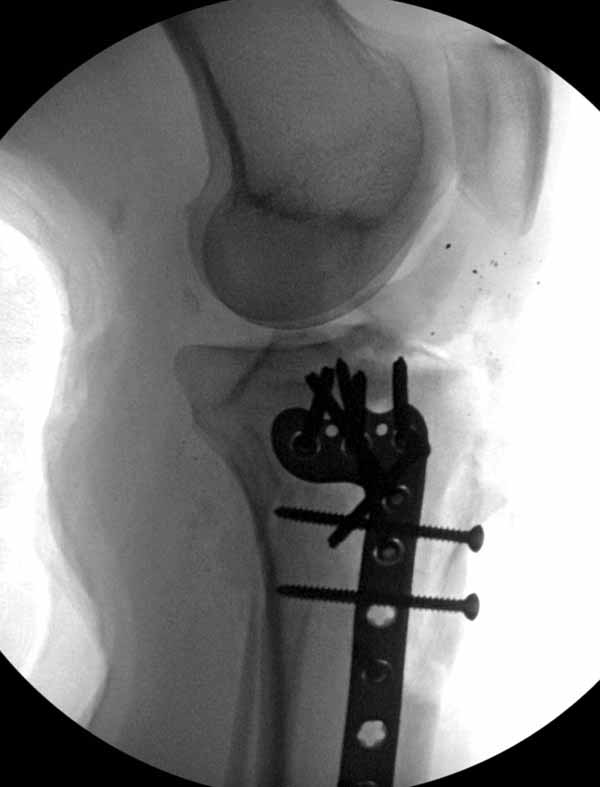

Из всех перечисленных методов подходит вариант пластики аутокостью и усиление (арматура) шурупами. Основная задача сохранить интактную медиальную стенку и латеральный кортекс. Доступ передне-латеральный, но надо работать спереди шейки через небольшое окно в 10-15 мм. Фиксацию надо проводить между медиальной тонкой стенкой головки и латеральным кортексом. Каннюлированные шурупы 6.5 мм очень грубые и могут разрушить остаток стенки. Фиксировать надо кортикальными шурупами 3.5 мм, которые создадут мостик и арматуру в шейке. Провести по периметру шейки 4, и в центре пару шурупов. Во время операции и при манипуляции соблюдать осторожность, в любой момент может наступить стресс перелом. Заранее надо заказывать длинные шурупы!

Рентген контроль каждые 4 недели и полную нагрузку на конечность можно разрешить через 12 недель, а через 6 недель в 50% .